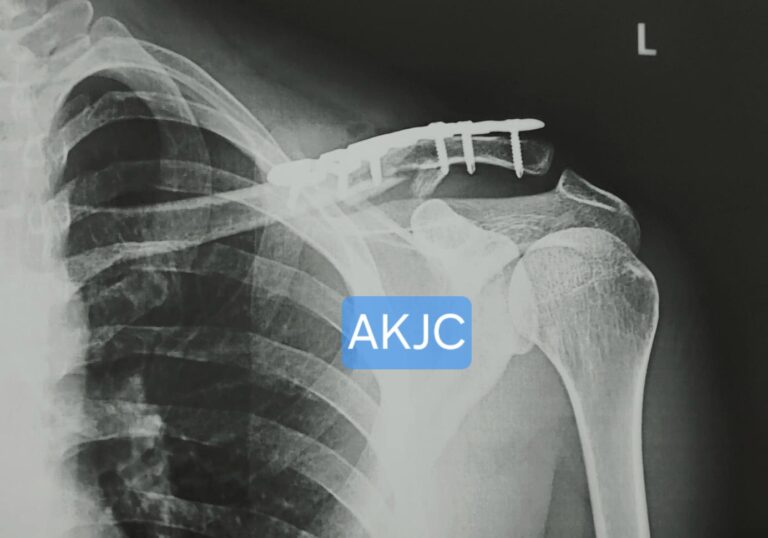

Intra-operative image showing surgical fixation for Clavicle Fracture Treatment in Indore using anatomical plate and screws to restore normal bone alignment.

This method provides strong and stable fixation, allowing early shoulder mobilization. It also helps maintain proper bone length and alignment, which reduces the risk of deformity or non-union. In most cases, the implant does not need to be removed unless it causes irritation.

Case 2 - 15 year old patient with Fracture Collarbone - locking plate fixation done in Indore